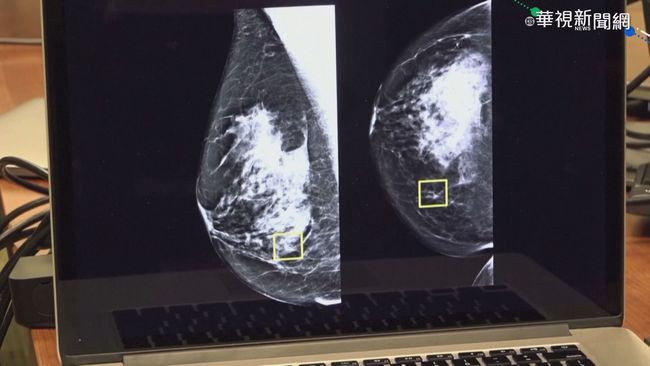

黃醫師特別說明,雖然九成乳房腫塊屬於良性,包括纖維囊腫、水泡或發炎,但一般人難以自行分辨。當腫塊大到能觸摸時,通常已接近2公分。若發現不會痛的硬塊且月經過後仍持續存在,或在腋下發現任何大小的硬塊,都必須高度警覺盡速就醫。乳房纖維囊腫常見於30至50歲女性,雖屬良性但可能與乳癌同時存在,不可輕忽。

台北市衛生局列出八大高風險族群,包括具家族病史、單側曾罹癌、曾患卵巢癌或子宮內膜癌、30歲後才生育或未生育、未曾哺乳、初經早或停經晚、長期使用荷爾蒙補充劑、中年後肥胖,以及經常食用高脂肪食物者,都應定期接受篩檢,及早發現及早治療。